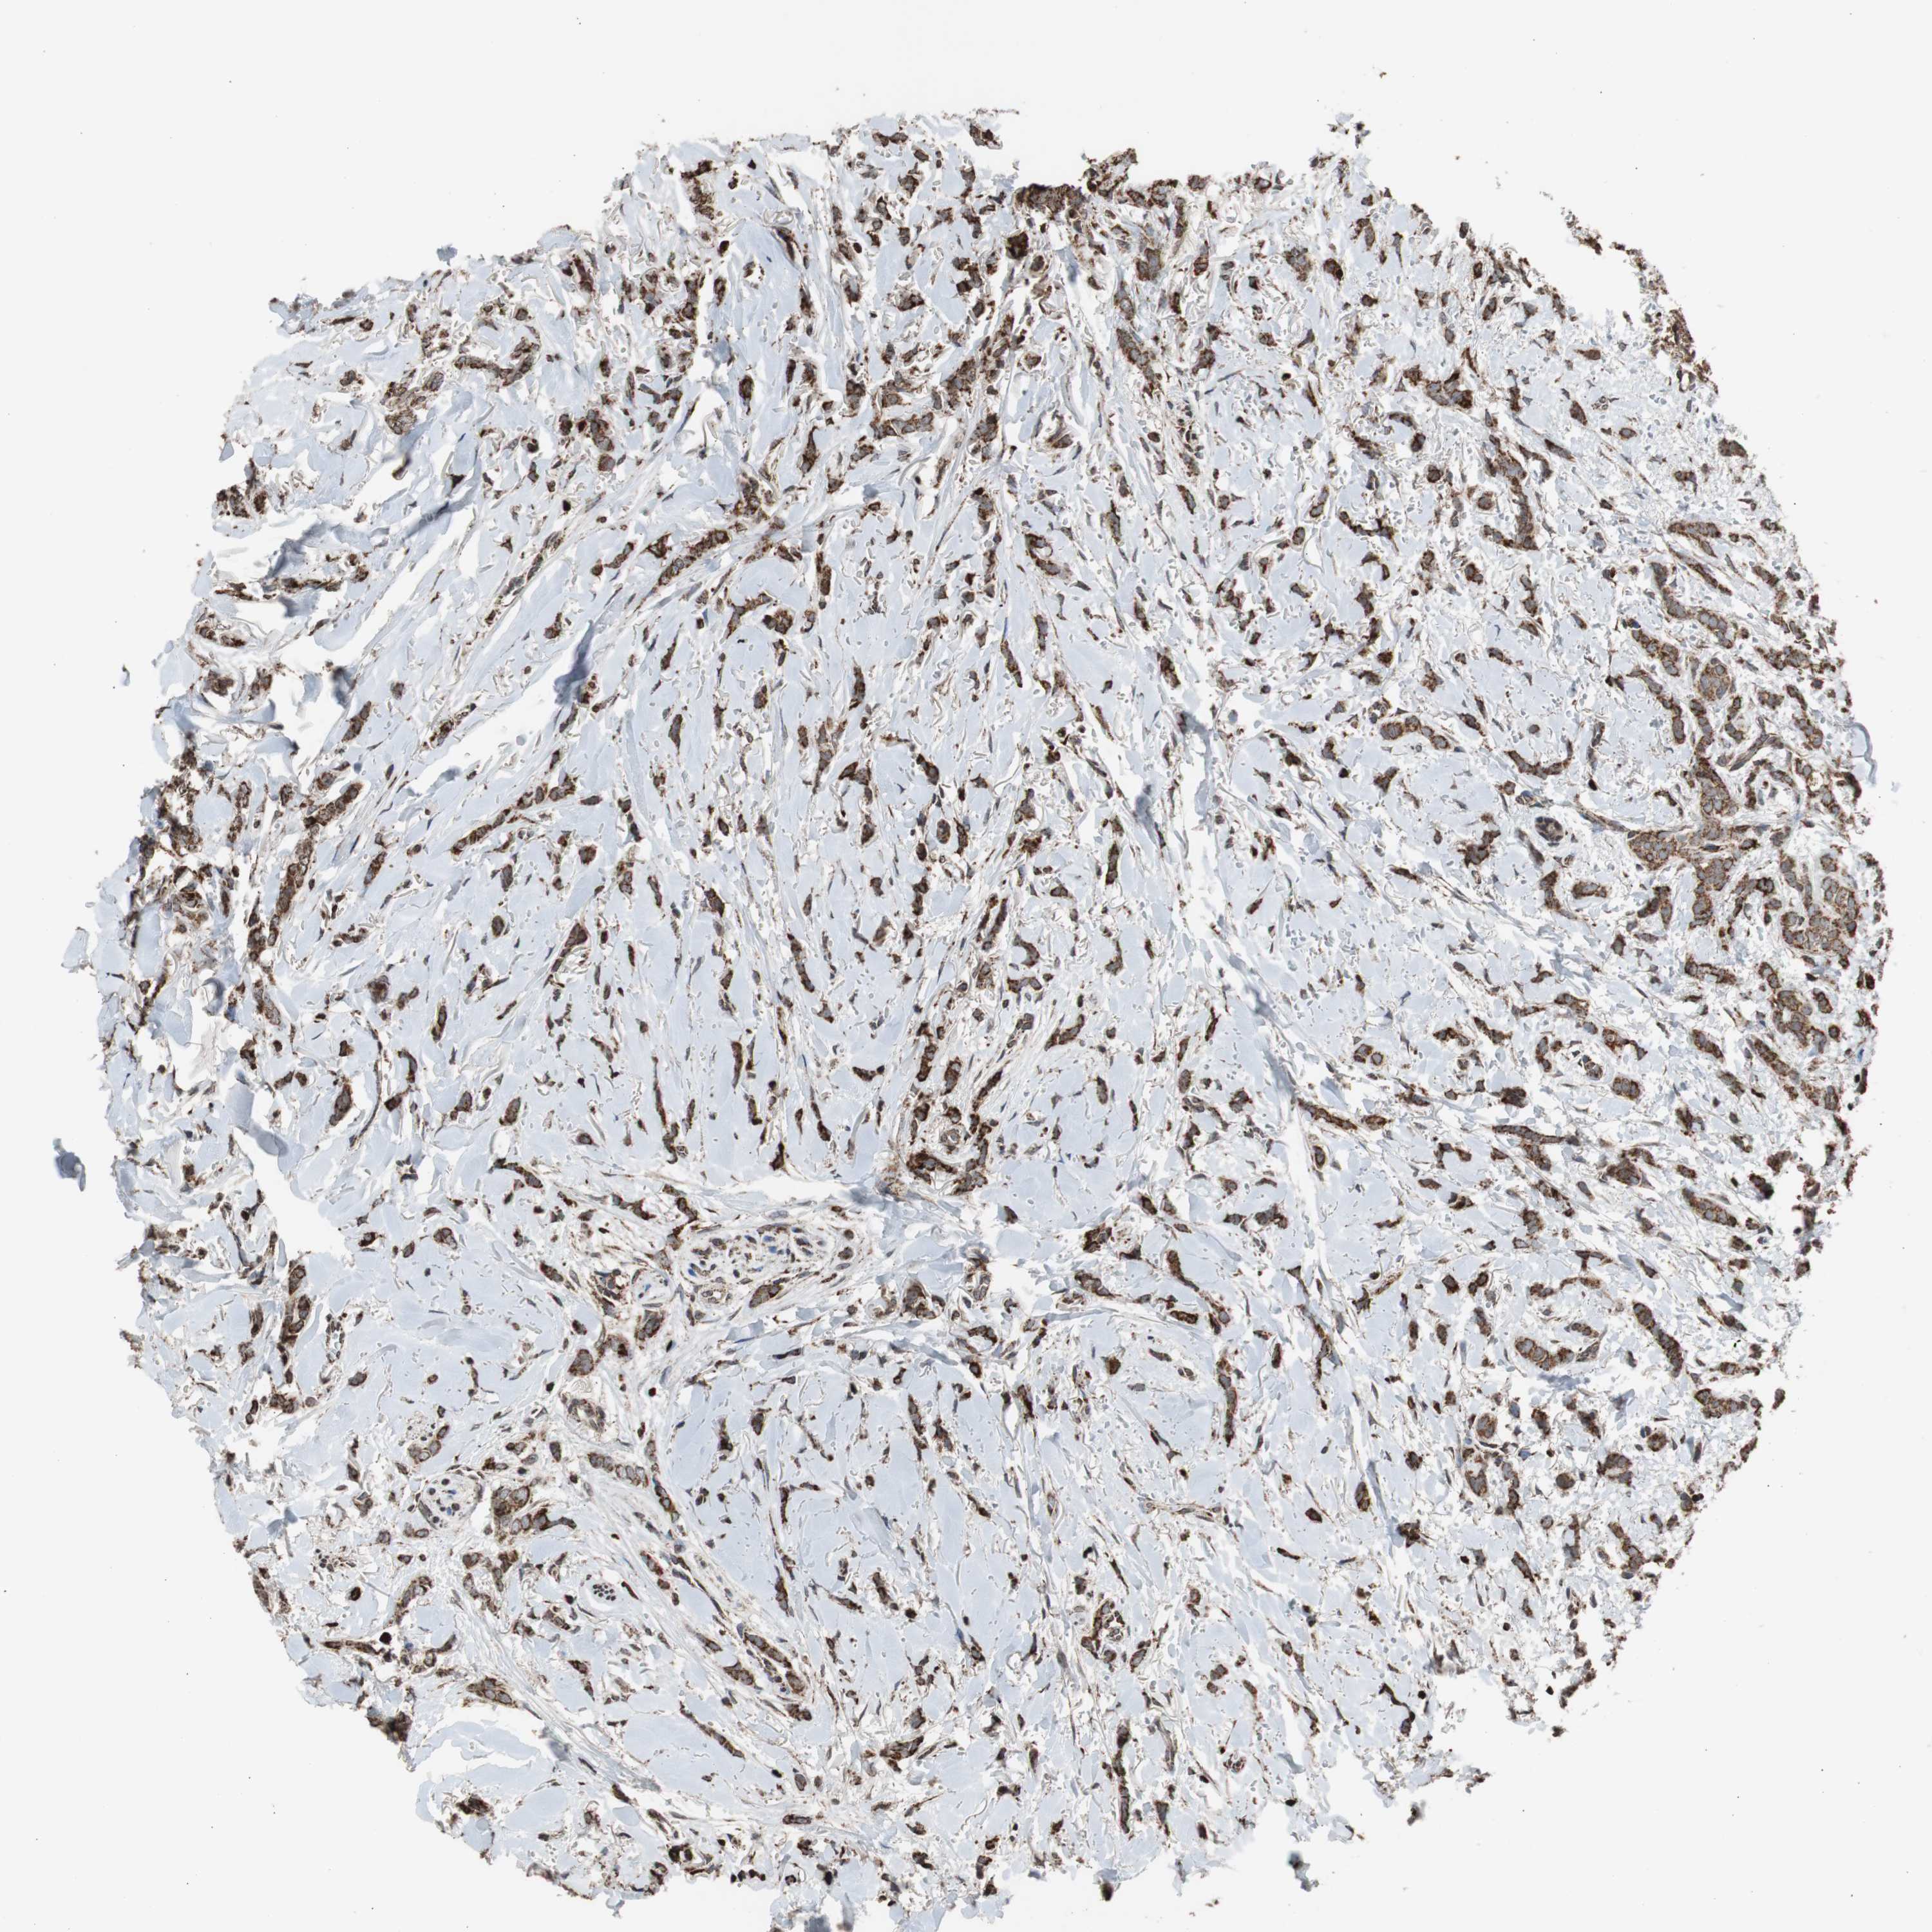

CANCER BREAST CANCER Show tissue menu

BRCA TCGA BRCA VALIDATION PROTEIN EXPRESSION